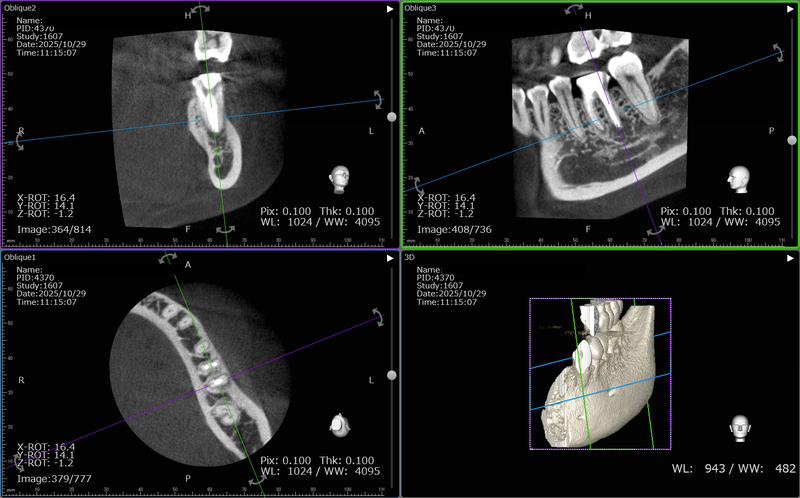

術前のCTです。

歯根の周囲の骨吸収が認められます。

根管治療後のCTです。

歯根の周囲の骨吸収もだいぶ改善されました。